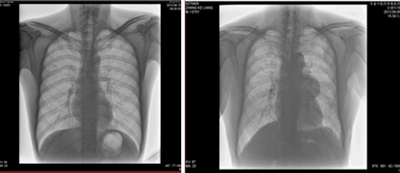

★全身各部位透視(如胸透、腹透等)、透視下定位、透視下穿刺及透視下數(shù)字點片攝影。